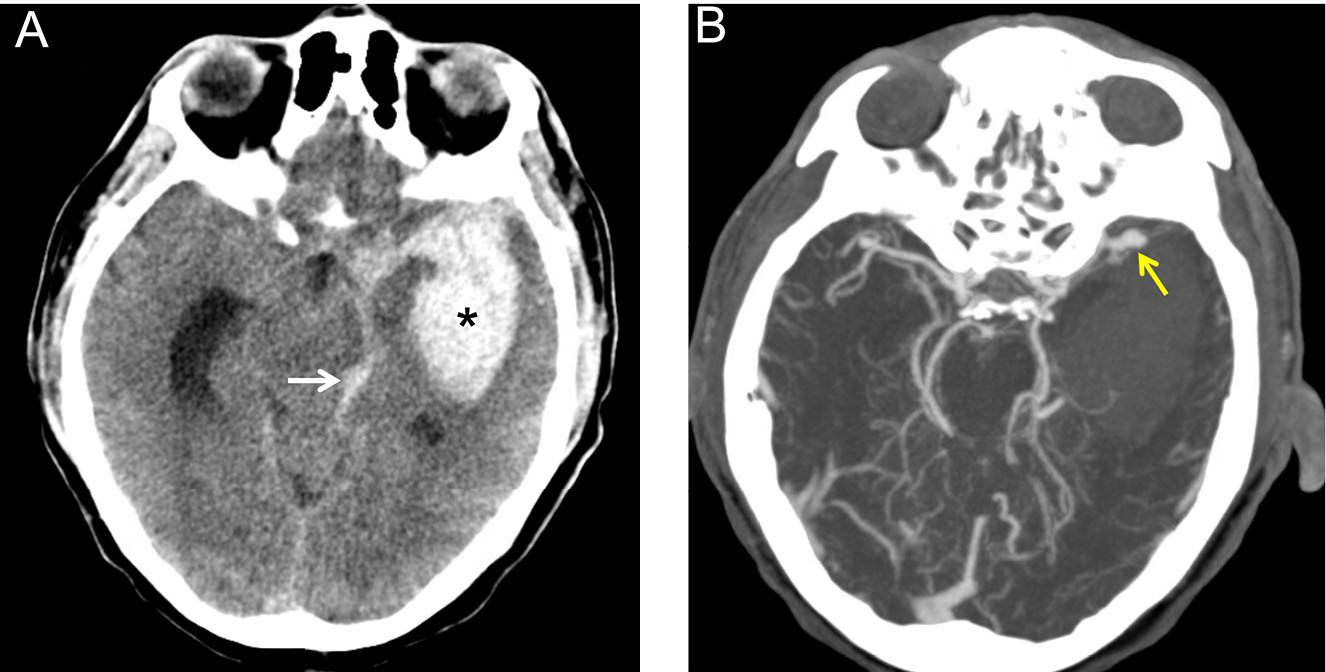

Because of its high sensitivity and ready availability, non-contrast head CT is the most common imaging modality used in the ED to diagnose SAH.7 SAH appears as hyperdense material in the subarachnoid space on non-contrast CT. (See Figure 1A.) Given that most (70%) cerebral aneurysms occur at the anterior, middle, and posterior cerebral arteries, aneurysmal bleeding often surrounds the basal cisterns.7,21 (See Figure 1B.) With time, as blood proteins diffuse or become absorbed or degraded, SAH becomes isodense to brain tissue, and non-contrast head CT becomes less sensitive.7,14

Figure 1. Left Middle Cerebral Artery Aneurysm |

(A) Non-contrast head computed tomography of a 52-year-old man presenting with a thunderclap headache after jogging. Hyperdense blood (star) is seen in the left basal ganglia and internal capsule, with intraventricular extension (arrow). |